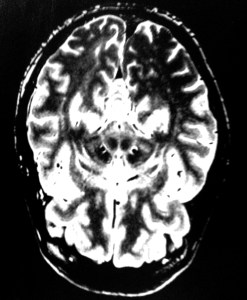

I mention this because just recently (as a long term user of Leva Dopa the main anti Parkinsons drug, whose side effects include hallucinations ) I’ve been getting them too and and it is very wierd. I als often get the the feeling that somebody is always behind my shoulder. Also, any small bits of detritus, crumbs etc will often appear to my cauliflower brain as scuttling little insects.